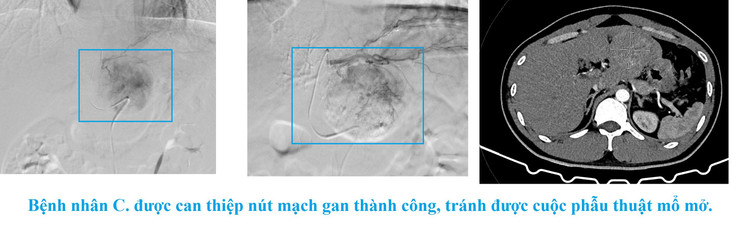

Nhờ phát hiện sớm - chẩn đoán chính xác - xử trí kịp thời, bệnh nhân Nguyễn Văn C. đã được chuyển viện an toàn. Bệnh nhân C được thực hiện can thiệp nút mạch gan tại Bệnh viện Đa khoa tỉnh Quảng Ninh kịp thời, tránh được được cuộc phẫu thuật mổ mở. Hiện tại, sức khỏe ổn định.

Ca bệnh này là minh chứng rõ nét cho hiệu quả của công tác hội chẩn liên khoa và năng lực chuyên môn của đội ngũ bác sĩ Bệnh viện Đa khoa khu vực Cẩm Phả trong việc phát hiện sớm, xử trí nhanh các tình huống cấp cứu nguy hiểm. Chuyển tuyến kịp thời, đảm bảo bệnh nhân được can thiệp nút mạch cầm máu sớm, bảo toàn sinh mạng.